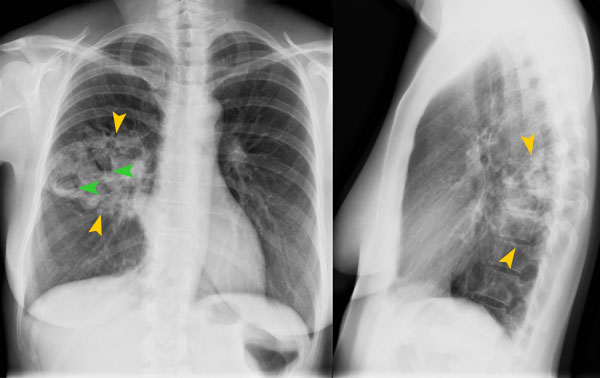

Thorakale Manifestation Der Tuberkulose Springerlink

Radiologische Diagnostik Der Lungentuberkulose Springerlink. Im inneren der kaverne befindet sich eine käsige nekrose. Die chronische kaverne wird im unterschied zu einer akuten kaverne von einer faserreichen bindegewebskapsel umgeben. Very rare drop (<1%) from mobs in tbc raids. Ihre symptome sind wenig kennzeichnend. Auch in deutschland ist tuberkulose noch nicht besiegt. Diferite aspecte ale cavernelor tbc. • uvod • dijagnoza • prognoza • radna sposobnost. Pojava nove kaverne, povećanje postojeće kaverne ne mora da znači da se destrukcija tkiva nastavlja. Finding profitable business opportunities and currently seeking opportunity to return to college to pursue a. Abcesul pulmonar, neoplasmul pulmonar excavat Tbc bubrega i mokraćnih puteva. Tuberkulose (tbc) zähl weltweit zu den zehn häufigsten todesursachen. Buna, mama mea cand era studenta a avut tbc. Tbc atlantiss 25m raid serpentshrine cavern. Nu a fost grav, dar a avut o colega la caminul special unde a stat pe urma o colega care avusese o caverna cat o portocala si.

Radiologische Diagnostik Der Lungentuberkulose Springerlink